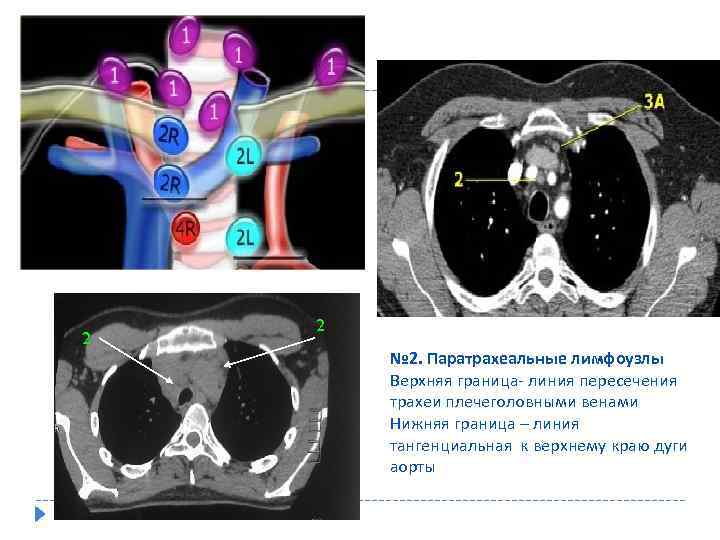

2 2 № 2. Паратрахеальные лимфоузлы Верхняя граница- линия пересечения трахеи плечеголовными венами Нижняя граница – линия тангенциальная к верхнему краю дуги аорты

2 2 № 2. Паратрахеальные лимфоузлы Верхняя граница- линия пересечения трахеи плечеголовными венами Нижняя граница – линия тангенциальная к верхнему краю дуги аорты

Классификация лимфоузлов средостения 1. Верхние медиастинальные 2. Верхние паратрахеальны. 3. Преваскулярные и ретротрахеальные 4. Ретротрахеальные 5. Нижние паратрахеальные 6. Подаортальные ( аортолегочное окно ) 7. Парааортальные лимфоузлы 8. Субкаринальные 9. Параэзофагеальные 10. Легочной связки 11. Корневые 12. Междолевые 13. Долевые 14. Сегментарные 15. Субсегментарные.

Классификация лимфоузлов средостения 1. Верхние медиастинальные 2. Верхние паратрахеальны. 3. Преваскулярные и ретротрахеальные 4. Ретротрахеальные 5. Нижние паратрахеальные 6. Подаортальные ( аортолегочное окно ) 7. Парааортальные лимфоузлы 8. Субкаринальные 9. Параэзофагеальные 10. Легочной связки 11. Корневые 12. Междолевые 13. Долевые 14. Сегментарные 15. Субсегментарные.